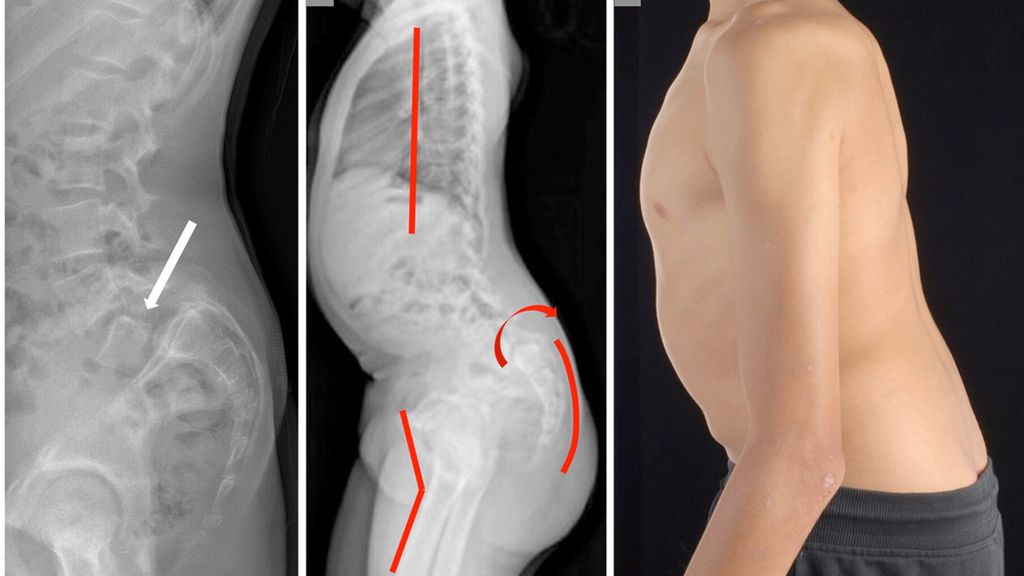

Nebst einer allgemeinen dynamischen und statischen orthopädischen Untersuchung muss eine dezidierte Beurteilung der Wirbelsäule einschliesslich einer neurologischen Untersuchung durchgeführt werden. Typisch für die Spondylolyse sind reproduzierbare, meist klar umschriebene und als stechend beschriebene lumbosakral lokalisierte Schmerzen bei forcierter Extension (Reklination) der LWS. Neurologische Auffälligkeiten sind selten nachweisbar. Bei Vorliegen einer Spondylolisthese kann manchmal eine Stufe zwischen den Dornfortsätzen der unteren LWS getastet werden. Ein hochgradiges Wirbelgleiten führt durch die zunehmende segmentale Kyphosierung zu einer relevanten Störung des sagittalen Profils der Wirbelsäule mit typischen, klinisch objektivierbaren Kompensationsmechanismen wie Abflachung der Brustwirbelsäule, Retroversion des Beckens/Sakrums bis hin zu zunehmender Hüft- und Kniebeugung zur Aufrechterhaltung der sagittalen Gesamtbalance (Abb. 2).

Abb. 2: Bild (a) zeigt ein stehendes seitliches Röntgenbild der Lendenwirbelsäule (LWS) mit hochgradiger Spondylolisthese von LWK5 gegenüber SWK1. Die Abbildungen (b) und (c) zeigen radiologisch und klinisch die mit der Zeit möglichen Kompensationsmechanismen bei hochgradigem Wirbelgleiten mit Abflachung der Kyphose der BWS, Retroversion des Beckens sowie Hüft- und Knieflexion zum Erhalt der sagittalen Balance